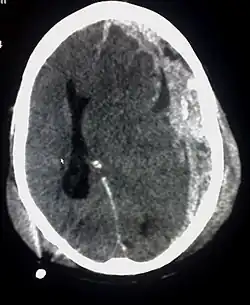

Krwiak podtwardówkowy

| haematoma subdurale | |

Pourazowy krwiak podtwardówkowy | |

Krwiak podtwardówkowy (łac. haematoma subdurale, ang. subdural haematoma) – nagromadzenie wynaczynionej krwi pomiędzy oponą twardą a pajęczynówką. Krwotok do przestrzeni podtwardówkowej jest zazwyczaj następstwem ciężkiego uszkodzenia mózgu.

Rozpoznanie opiera się na wynikach badań neuroobrazowych, np. tomografii komputerowej lub rzadziej śródoperacyjnie.